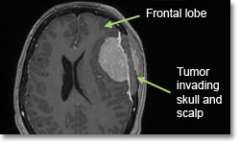

- If the tumor invades any of the large draining veins, major arteries on the brain surface, or if it is on the underside of the brain, chances of a complete resection decrease and risk of complications increases.

- Meningioma tumors that are near the surface and have not invaded deep structures or major blood vessels are more likely to be totally removed safely.